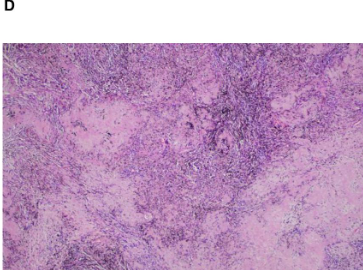

术后病理

术后病理证实为ypT0N0M0,13枚清扫淋巴结(5-7组、10-12组)均无肿瘤累及;镜下未见残留肺腺癌细胞,仅见局灶凝固性坏死、纤维组织增生及淋巴细胞浸润。